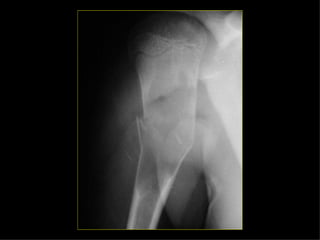

Tipos Fractura patológica.  Causa local (carcinoma metastásico), suelen ocurrir a nivel de los cuerpos vertebrales, 1/3 proximal del fémur y ½ proximal del húmero.  Causa generalizada (osteoporosis senil), con afectación fundamental en los cuerpos vertebrales dorsales y lumbares, así como el cuello del fémur. Enfermedad local. Tumores benignos. Encondroma. Tumores  malignos. Ca. Metastásico. Infección. Osteomielitis. Otros. Quiste simple. Displasia fibrosa. Granuloma eosinófilo. Lesiones difusas. Congénitas. Ostg. Imp. Adquiridas. Varios.

CADERA FEMUR RODILLAPIERNA TOBILLO PIE Eversión Inversión